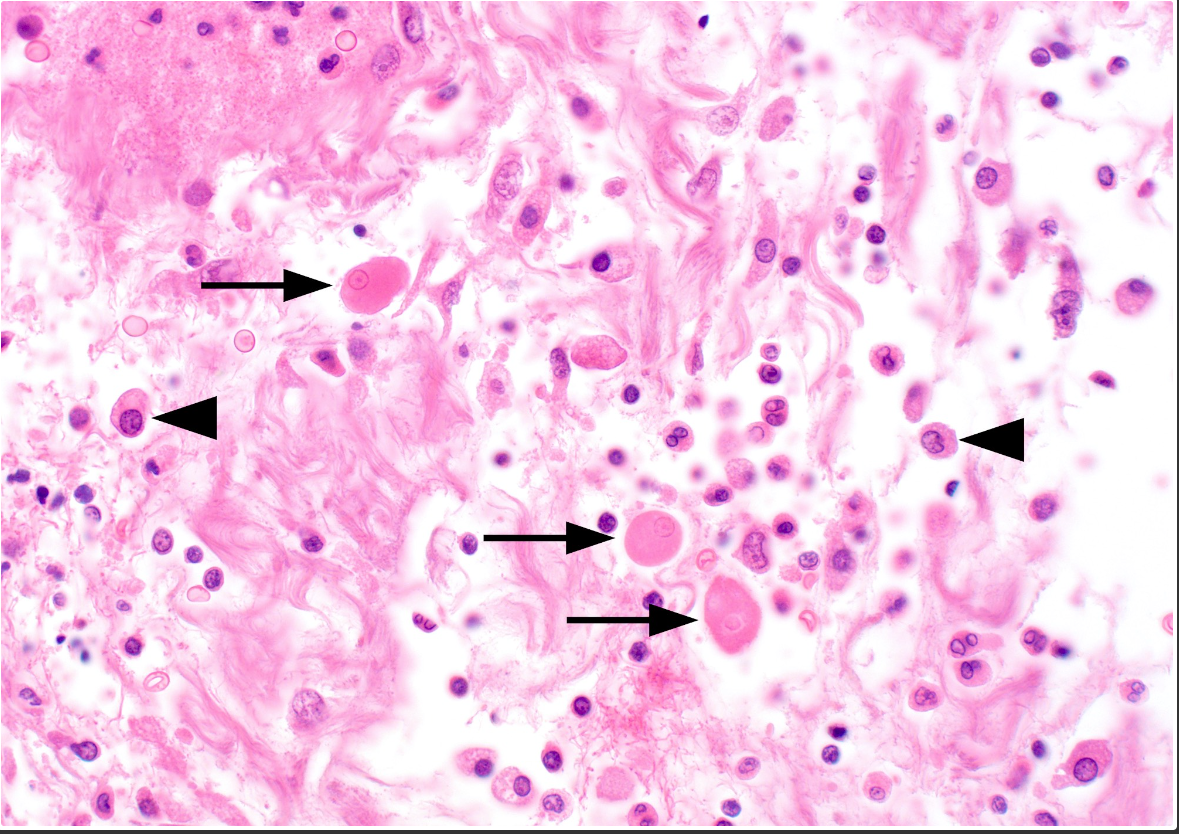

Entamoeba histolytic colitis

Characteristic flask shaped of amoebic ulcer. Trophozoites are commonly seen at the interface of the necrotic and viable tissue.

Below: Several infiltrating trophozoites (arrows) with abundant dense cytoplasm and a small round nucleus are seen in this case of ulcerative amebic colitis. Although they may be confused with macrophages, their nuclear features allow them to be easily identified from surrounding host inflammatory cells. (distinctive round nucleus with peripherally condensed ring of chromatin and central dot-like karyosome)